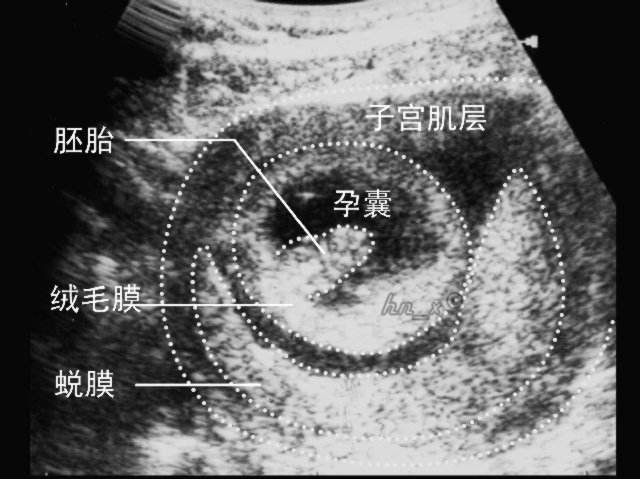

什么是“孕囊”

当受精卵着床后,子宫内膜会迅速“蜕膜”,蜕化下来的内膜会把受精卵覆盖并包围在子宫肌肉和内膜之间,受精卵就在这个封闭的囊内慢慢的发育成胎儿,这就是医生常说的“妊娠囊”,也就是我们常说的孕囊。

一般在女性停经5周(大约同房后3周左右)时,正常情况下可以通过阴超,看到明显的孕囊回声,怀孕6-8周时,在孕囊里可以看到卵黄囊、胚芽及胎心搏动,说明胎儿发育的好。